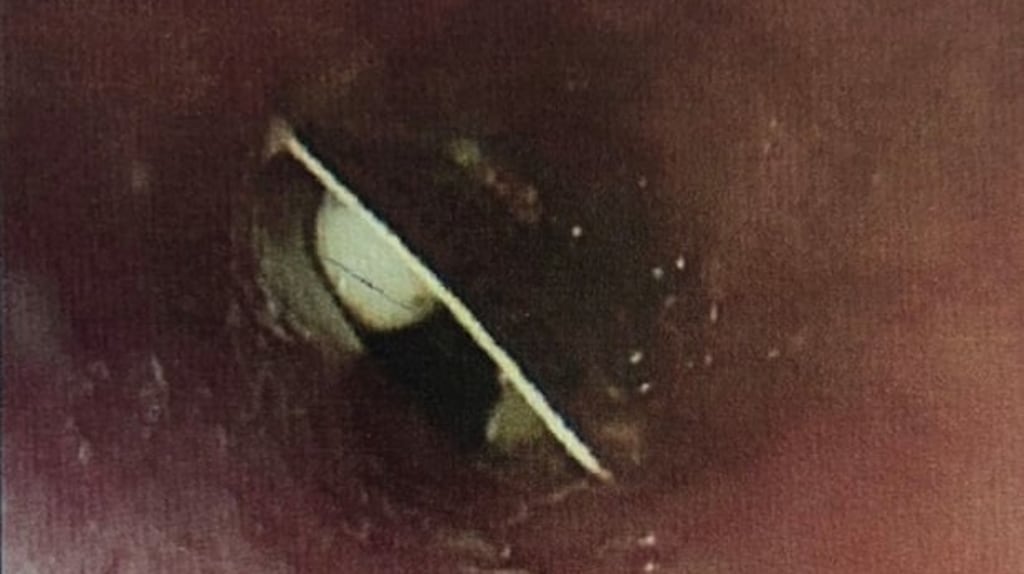

The pill packet was finally detected during an outpatient appointment using an oesophagogastroduodenoscopy scan, which examines the upper intestinal tract using a lighted tube.

The pill packet was then safely removed.

"She had swallowed her tramadol tablets whole in the original foil packet which was lodged in the upper oesophagus," said the BMJ case report. "She underwent rigid oesophagoscopy and removal of foreign body uneventfully (17 days after ingestion of her tablets) and she was discharged after a period of observation."